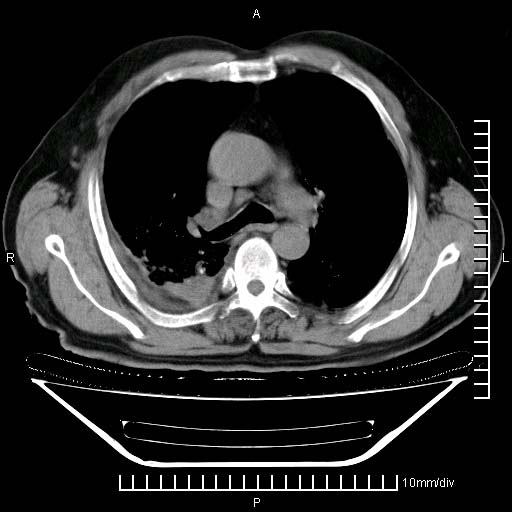

既往肺结核,近10几天,咳嗽,咳痰,右侧胸痛,疼痛较明显,右上肺斑块考虑结核灶胸膜粘连,增强,可惜动脉期没有定好,未见强化,可延迟4分后又见较明显强化,中心见低密度影,如果说结核是边缘强化,可这个灶强化的面积挺大的,让人很挠头。

1)两肺继发性肺结核。2)右侧胸膜增厚+少量胸腔积液。